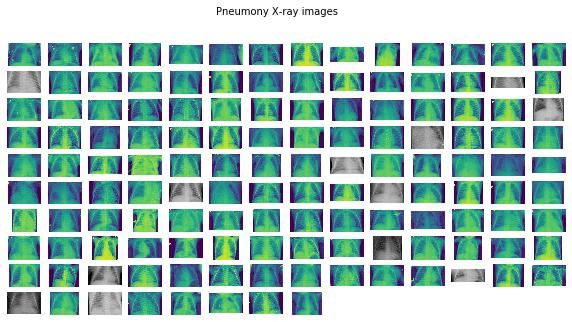

这样,我们调用可视化支持函数,检查得到的结果:

pneumo_images = list(paths.list_images(f"{dataset_path}/pneumo"))covid_images = list(paths.list_images(f"{dataset_path}/covid"))plots_from_files(covid_images, rows=10, maintitle="Covid-19 X-ray images")

plots_from_files(pneumo_images, rows=10, maintitle="Pneumony X-ray images"

图像看起来不错。